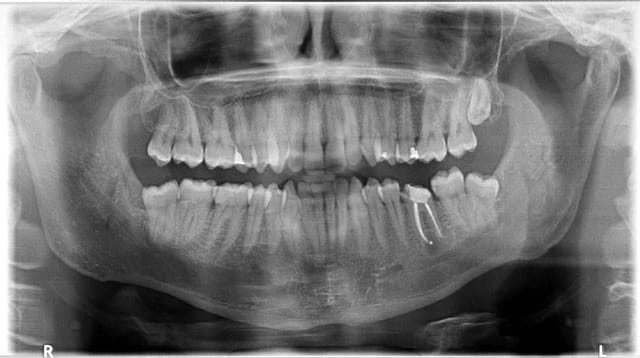

J'ai pas mis la digue en endo pendant mes 5 ans de collaboration. J'ai dévitalisé une 36 à mon frère jumeau que j'ai couronné ensuite (j'aurais du faire un inlay ou un compo mais à cette époque je couronnais toutes dents dévitalisées. J'ai quand même évité l'inlay core...)

Bref, un an plus tard 2 belles pêches tellement grosses que les maxillo du service où il bosse affûtaient déjà les daviers...

J'ai repris l'endo avec digue ce coup ci et comme par hasard, guérison de la lésion.

Alors peut être que ça n'arrive que dans 3% des cas, mais pour celui à qui ça arrive c'est 100% chiant surtout quand on connait les chance de succès d'une reprise de traitement radiculaire quand y a des liaisons périapicales...